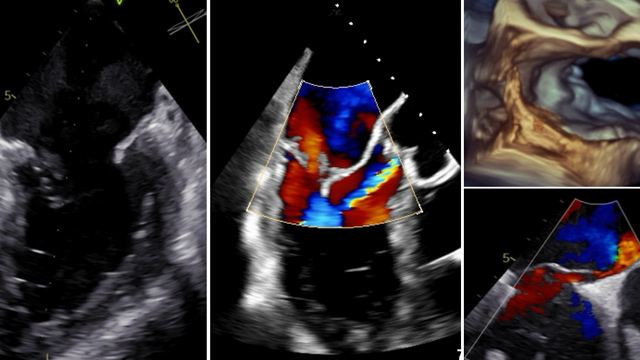

Featured cases - TAVI in unusual anatomical situations

Delve into a collection of TAVI cases in unusual anatomical situations, offering valuable insights for navigating complex scenarios. Discover successful percutaneous approaches to address conditions like bicuspid valves with membranous interventricular septum aneurysm, subaortic membrane, and pure aortic regurgitation in quadricuspid valves. Explore strategies for managing...